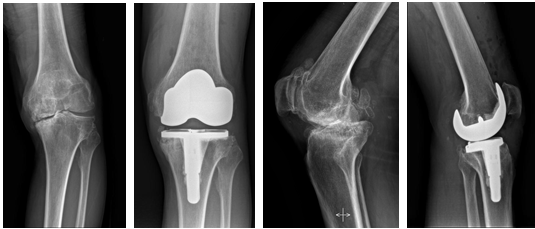

该数据集由.jpg 和 .dcm格式的膝盖 X 射线图像集合组成。根据不同的医疗状况将图像组织到文件夹中。每个文件夹都包含描述特定膝盖问题的图像。 数据集中的疾病和病症类型: 关节炎、骨折、骨关节炎第一阶段、骨关节炎第二阶段、骨关节炎第三阶段和骨关节炎第四阶段

该数据集由.jpg 和 .dcm格式的膝盖 X 射线图像集合组成。根据不同的医疗状况将图像组织到文件夹中。每个文件夹都包含描述特定膝盖问题的图像。

数据集中的疾病和病症类型:

关节炎、骨折、骨关节炎第一阶段、骨关节炎第二阶段、骨关节炎第三阶段和骨关节炎第四阶段